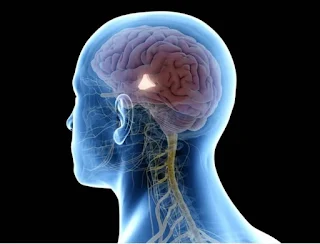

Bipolar disorder, a condition characterized by extreme mood swings ranging from manic highs to depressive lows, affects not only the individual’s mental health but also their relationships and sexual well-being. The complexities of bipolar disorder often intersect with intimate life in ways that can be challenging but manageable with awareness and support.

The Impact of Bipolar Disorder on Sexuality